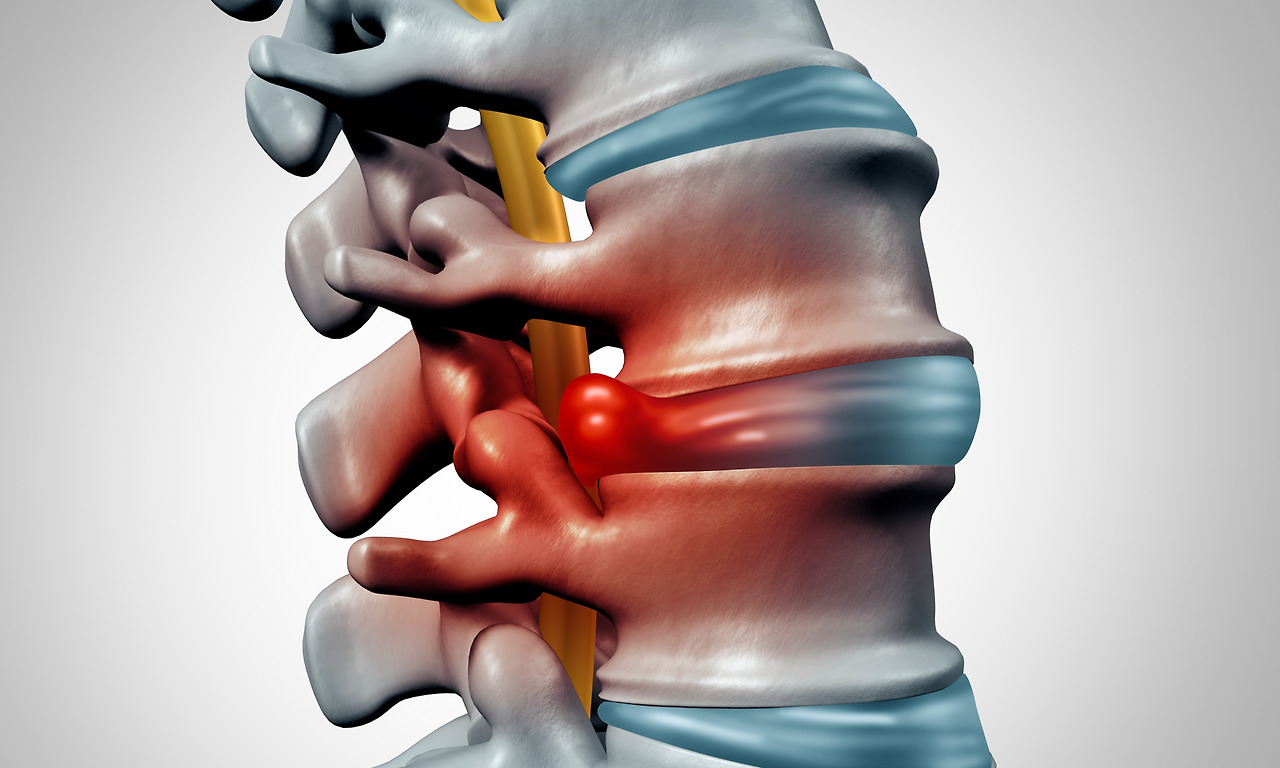

특히, 나이가 들면서 자연스럽게 나타나는 허리의 퇴행성 변화가 원인인 척추관협착증은 중년 이후에 나타나는 허리질환 중 하나입니다. 나이가 들며 신경다발이나 신경가지가 지나는 척추관(추간공) 주변의 뼈와 인대가 두꺼워지거나 디스크 퇴행으로 디스크가 제 위치를 벗어나면서 해당 공간이 좁아져 신경을 압박하는 것이지요.

IT_twi001t1879223.jpg

안정환 원장님“디스크와 척추관협착증 환자들은 다리로 가는 신경이 눌린다는 점은 비슷하지만 주원인이 다릅니다. 척추관협착증의 주원인은 퇴행성이지만 디스크는 외부의 큰 충격이나 잘못된 자세로 디스크가 튀어나와 염증이나 통증을 유발합니다”라고 허리디스크와 다른 척추관협착증의 발생원인을 알려주시네요.

추간공은 척추 사이의 구멍을 뜻합니다. 다시 말해 추골과 추골 사이에 있는 구멍으로 척추신경이 빠져나오는 공간이지요. 각종 신경절, 자율신경계, 혈관 등 생체 조직들이 지나가는 통로의 역할을 하는 추간공으로는 손상 혹은 노화된 디스크와 척추관 주변뼈에서 유리되어 나온 염증유발물질들도 빠져나가지요.

이런 역할을 하는 추간공은 척추 염증을 발생시키는 핵심적인 공간인데요. 추공간이 좁아지면 미세한 섬유성 유착들이 빠져나가지 못하고 추간공 내. 외측에 인대들과 신경이 얽히며 쌓이면서 염증과 통증을 일으킵니다.

IT_td0131t009951.jpg